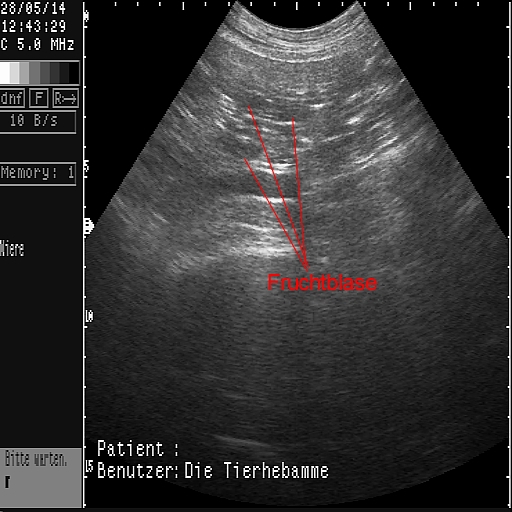

Das sind die ersten Ultraschallbilder vom 28.05.2014!

Es hat wirklich geklappt!

Die Tier-Hebamme hat 9 kleine Fruchtblasen gezählt...!!!

Wir haben die lange Wartezeit kaum ausgehalten und dann doch irgendwie geschafft! Mit einem positiven Ergenis, wie man an den Bildern sehen kann. Sage und schreibe neun kleine Fruchtblasen waren für das (geübte) Auge der Hebamme zu erkennen - wir haben nix gesehen....  Uns dafür aber unglaublich gefreut!!!!